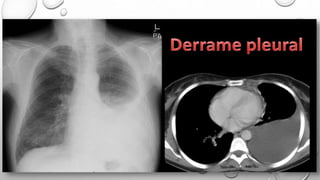

DIAGNOSTICO

Radiografia De

Tórax

Derrame pleural